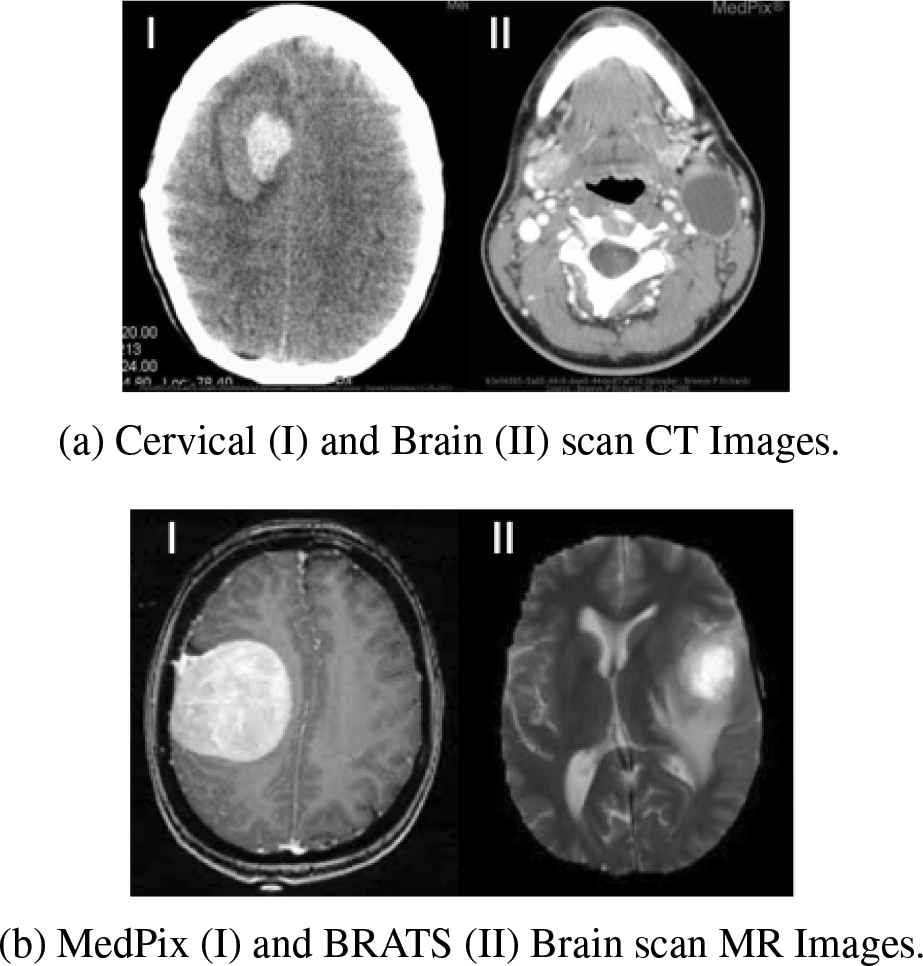

The reference medical input images used for qualitative analysis are shown in Figure 5. The segmentation results on these images are presented along with the edge map and ROI mask in row 1, row 2 and row 3, respectively. Similarly, the images segmented by adaptive KM, Fuzzy KM, PSO-KM, GA-KM and proposed method (WOA-KM) are presented in column A, B, C, D and E, respectively.

Reference medical images used for qualitative analysis.

5.1.1. Application to CT images

The performance of proposed method was first evaluated on CT brain scan image shown in Figure 5(a-I). This CT shows a hyper attenuating (white) mass lesion with two different densities, and a thin peripheral margin of lucency. Subsequently, it was evaluated on an axial CT image with branchial cleft cyst as shown in Figure 5(a-II). A low-density well-circumscribed lateral neck cystic mass can be seen in this CT at the peri-mandibular region of the left neck lateral to common carotid artery.

5.1.2. Application to MR images